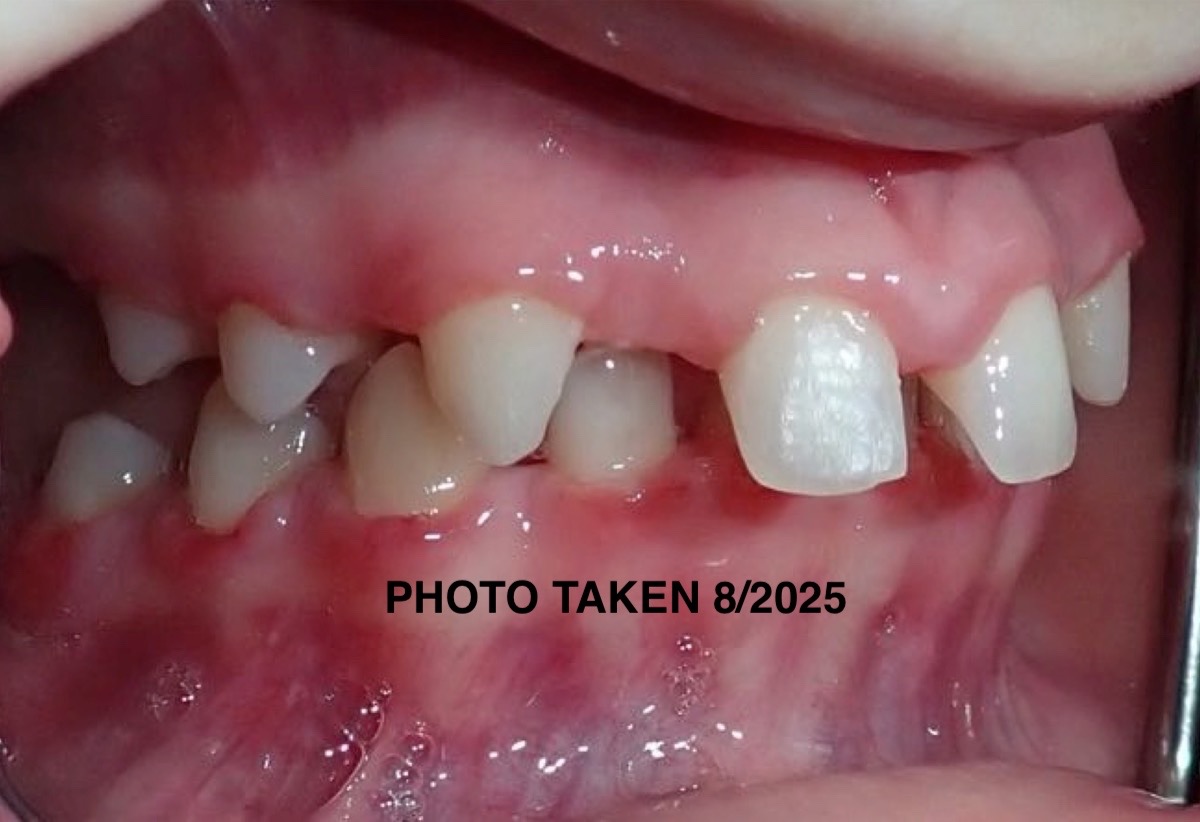

We were informed a few years ago that our daughter Laila is missing “14 permanent adult teeth” they just never came in. It is quite the anomaly and we are told by many specialists that she has a very unique situation and that this is not something that they have ever seen before or even see on a regular basis.

The diagnosis that they have so far given her is “Microdontia” a condition which the few teeth that did come in are abnormally small and not functional along with “Ogliodontia” being born without one or more permanent teeth (in her case 14 are missing). In conjunction with all the work that will need to be done to restore all of her teeth she will also be needing to undergo two extremely invasive surgical procedures, crown lengthening of the bone and enamel of her full mouth (removal of gums - scheduled in November 2025) and Mandibular advancement surgery a significant procedure where they will need to reconstruct her jaw due to certain abnormalities she was born with. There is also some speculation that she may possibly have a genetic disorder, called Pierre Robbin Sequence or Ehlos Danlos Syndrome and we are currently working with a Genetic Doctor to investigate all of this as well. The magnitude of all of this is daunting.

Nevertheless we have been navigating the beginning stages (PHASE 1) of what’s going to be many, many years of reconstruction and restoration of Laila’s mouth, jaw and teeth. The timeline was on a stand still for a while because they were waiting for her skull to fully develop so we are now at the point of being able to move forward. It is unfortunate to have to do all of this during her formative High School years but we just don’t have much of a choice and don’t want to prolong it as she has already been feeling the effects of not having a “normal” smile or a “functional” mouth to be able to chew food etc.

Laila is an extremely happy and positive young lady who doesn’t let any of these obstacles stop her from singing and performing on stage as her passion for Theater is strong! We hope to help her through this difficult journey with as much ease as possible so that she is able to continue her passions with grace but we are just not able to do it alone. Having a functional mouth (teeth/jaw) is so important for eating, speaking, singing and just quality of life, and the depth of this is immense and the end goal feels very lost to us right now.

Laila is truly dedicated to her future, our hope and wish for her is that she can feel good about herself as she continues to go through her young life and know that she doesn’t look strange or different and that she is able to have a normal and functional mouth/jaw/teeth someday when this is all said and done so that she is able to confidently shine her smile brightly on and off stage and have this all behind her while she is going through life. We just want her to be able to chew her food without any risk of choking or having to spit her food out while she is eating, the constant and painful locking of her jaw and severe migraines which all happens on a daily basis right now for her and that she will be able to have a future that doesn’t entail more than she’s already going to have to endure medically.